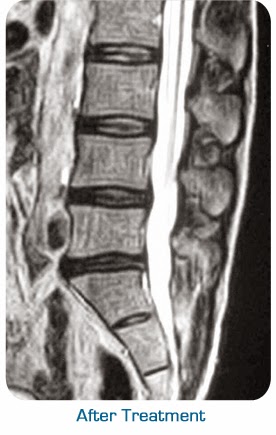

Category: Chiropractor